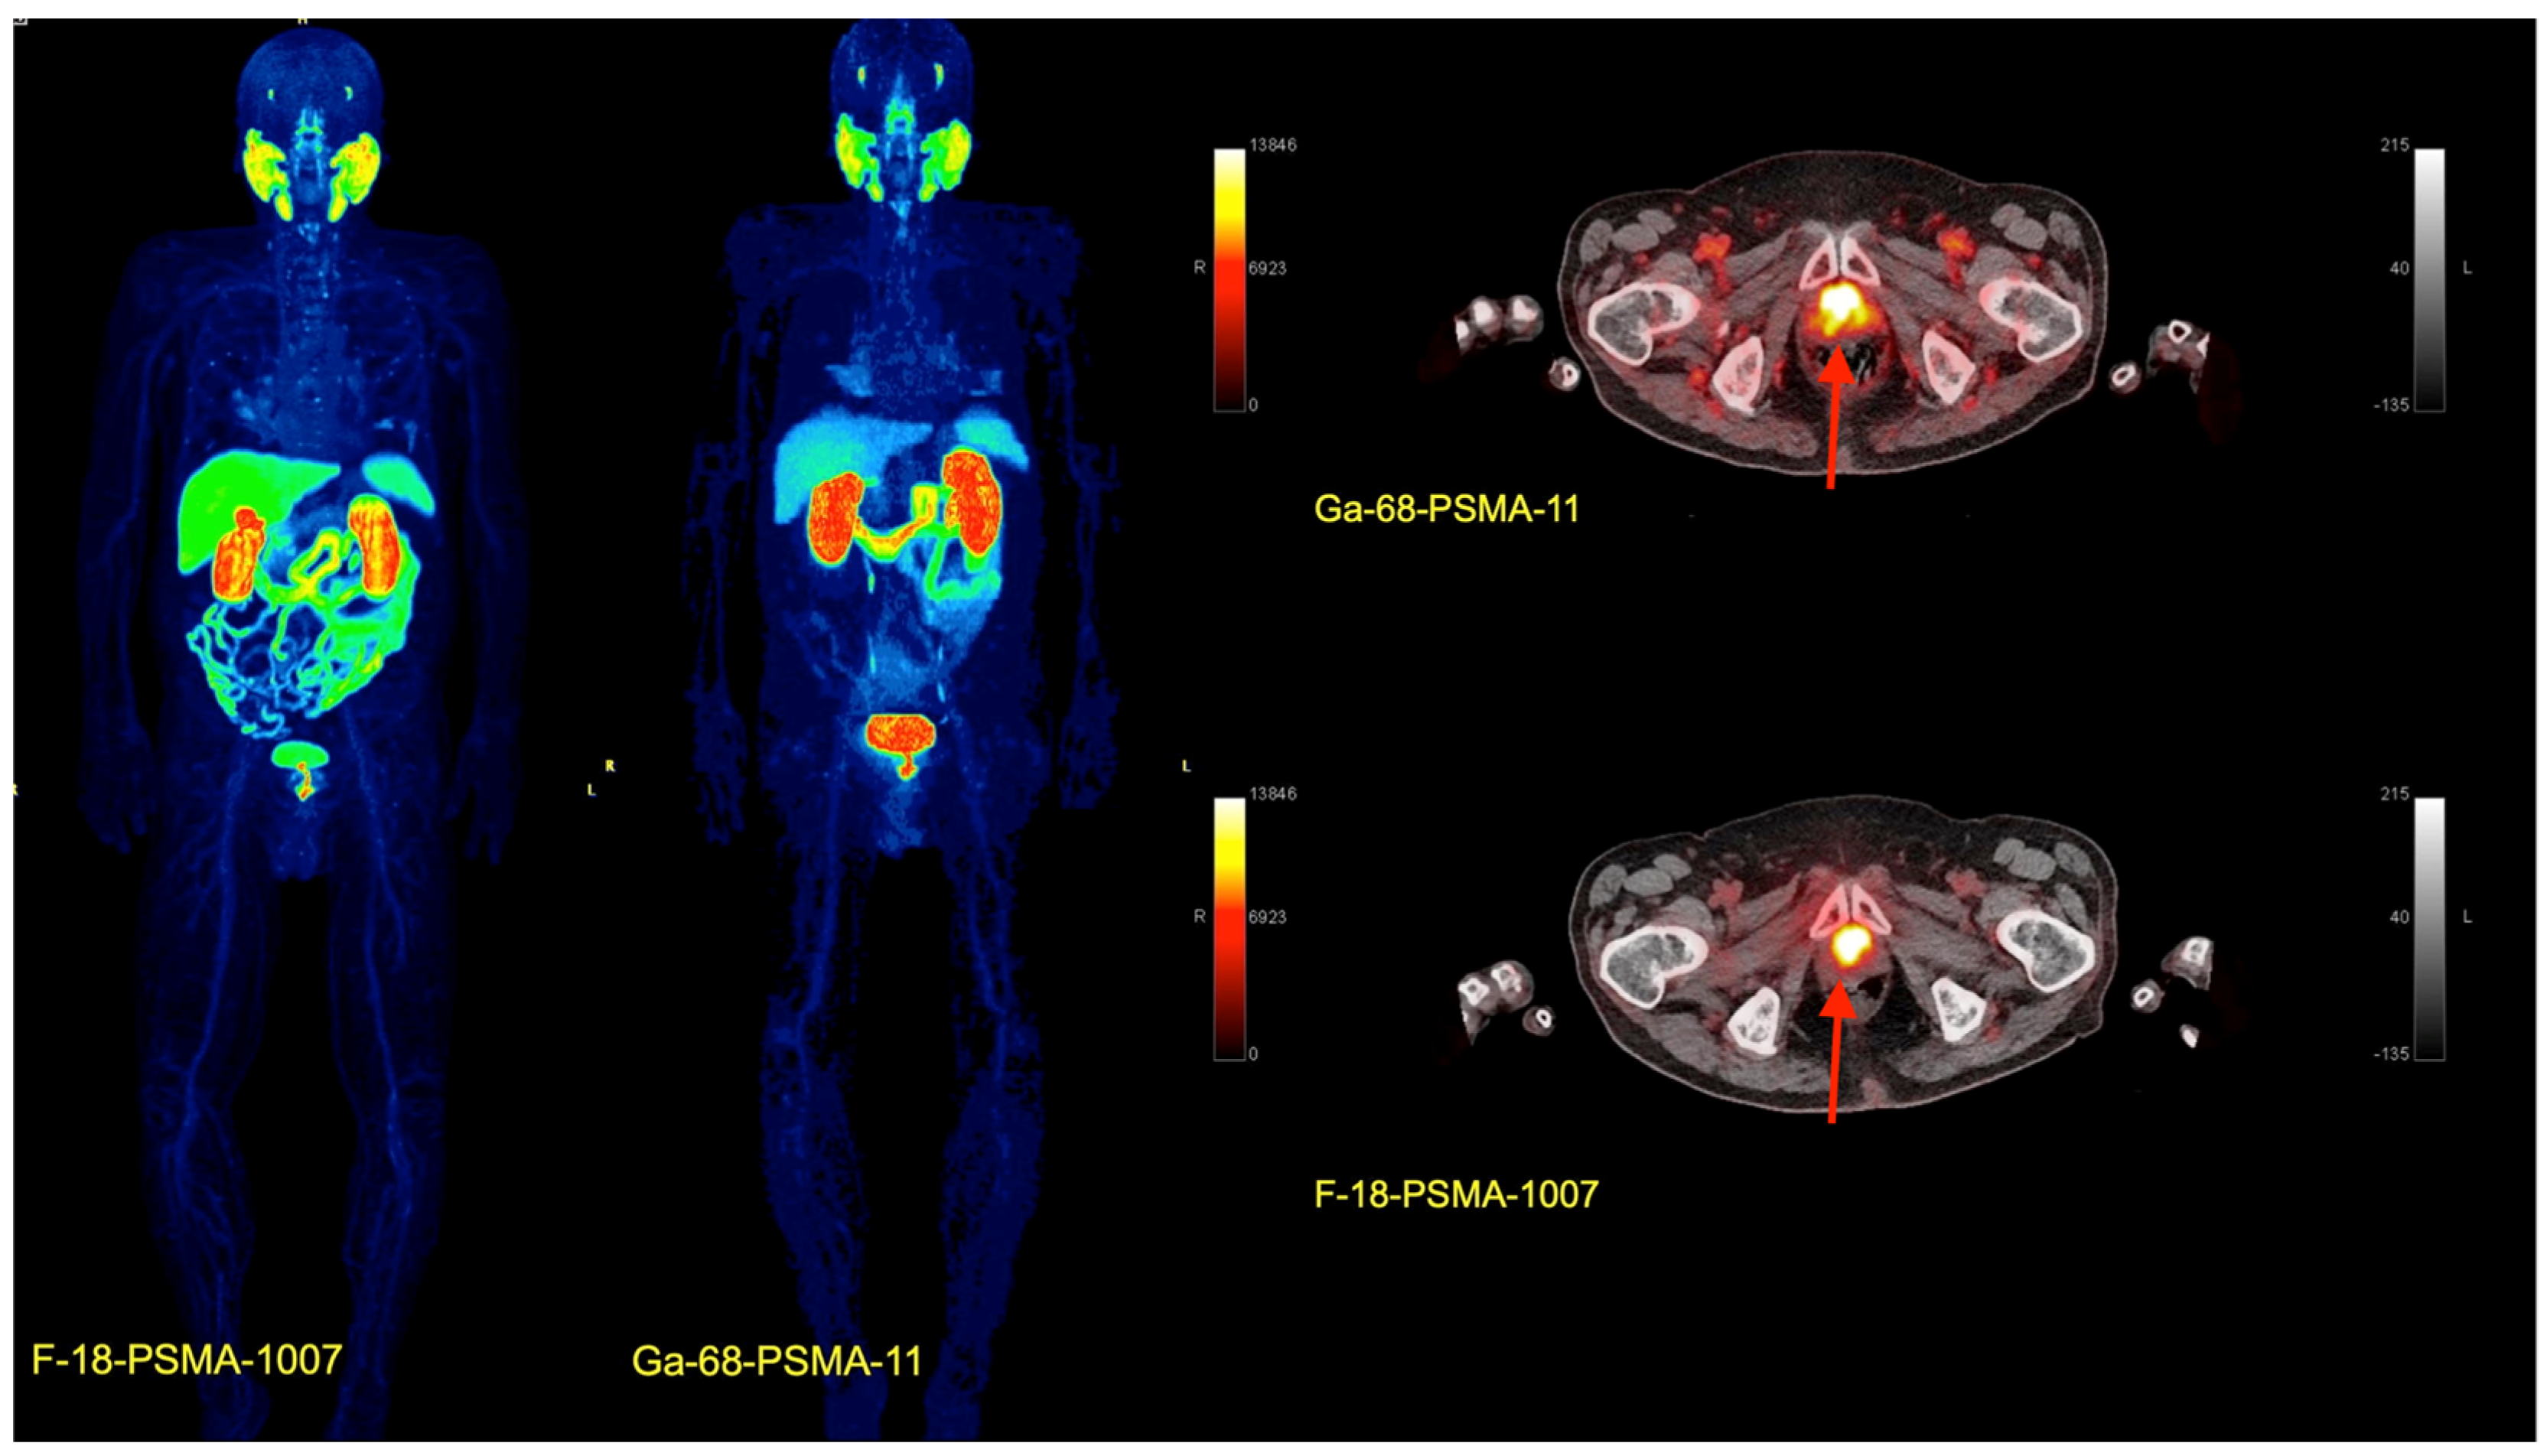

- Afshar-Oromieh, A.; Avtzi, E.; Giesel, F.L.; Holland-Letz, T.; Linhart, H.G.; Eder, M.; Eisenhut, M.; Boxler, A.; Hadaschik, B.A.; Kratochwil, C.; et al. The diagnostic value of PET/CT imaging with the 68Ga-labelled PSMA ligand HBED-CC in the diagnosis of recurrent prostate cancer. Eur. J. Nucl. Med. Mol. Imaging 2015, 42, 197–209. [Google Scholar] [CrossRef]

- Giesel, F.L.; Knorr, K.; Spohn, F.; Will, L.; Maurer, T.; Flechsig, P.; Neels, O.; Schiller, K.; Amarai, H.; Weber, W.A.; et al. Detection Efficacy of 18F-PSMA-1007 PET/CT in 251 Patients with Biochemical Recurrence of Prostate Cancer After Radical Prostatectomy. J. Nucl. Med. 2019, 60, 362–368. [Google Scholar] [CrossRef]

- Sartor, O.; de Bono, J.; Chi, K.N.; Fizazi, K.; Herrmann, K.; Rahbar, K.; Tagawa, S.T.; Nordquist, L.T.; Vaishampayan, N.; El-Haddad, G.; et al. VISION Investigators. Lutetium-177-PSMA-617 for Metastatic Castration-Resistant Prostate Cancer. N. Engl. J. Med. 2021, 385, 1091–1103. [Google Scholar] [CrossRef]

- Capasso, G.; Stefanucci, A.; Tolomeo, A. A systematic review on the current status of PSMA-targeted imaging and radioligand therapy. Eur. J. Med. Chem. 2024, 263, 115966. [Google Scholar] [CrossRef] [PubMed]